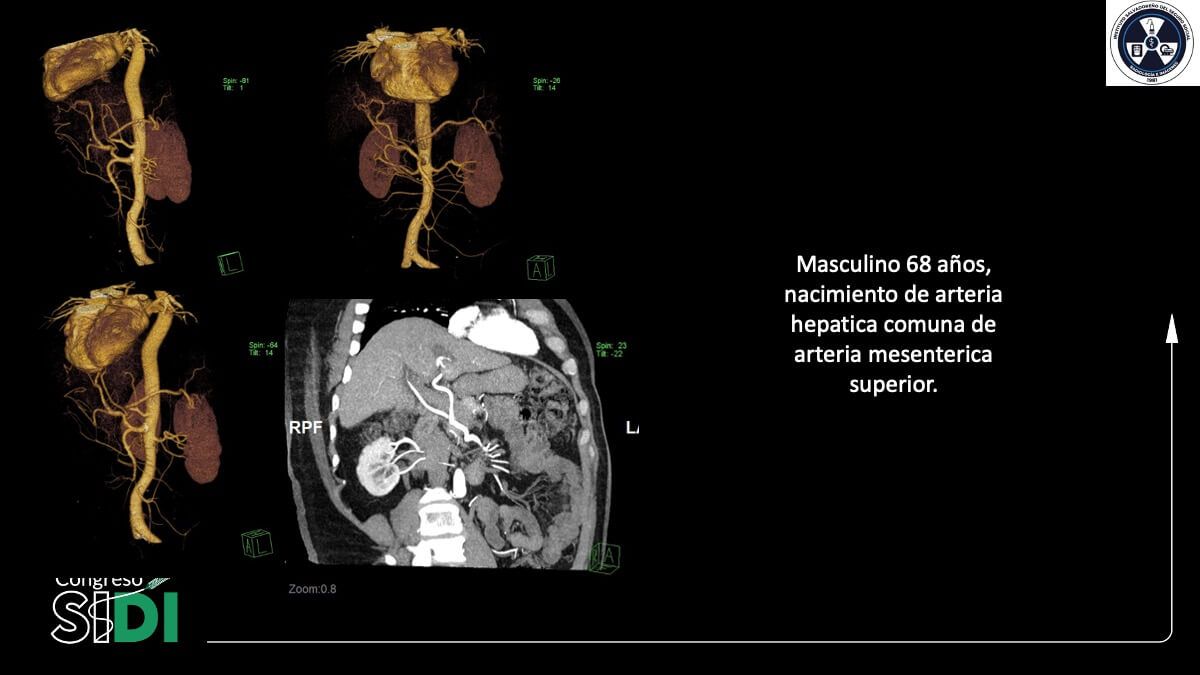

TACE en hepatocarcinoma con variaciones anatómicas arteriales: reporte de casos

Dr. David Alonso Melara